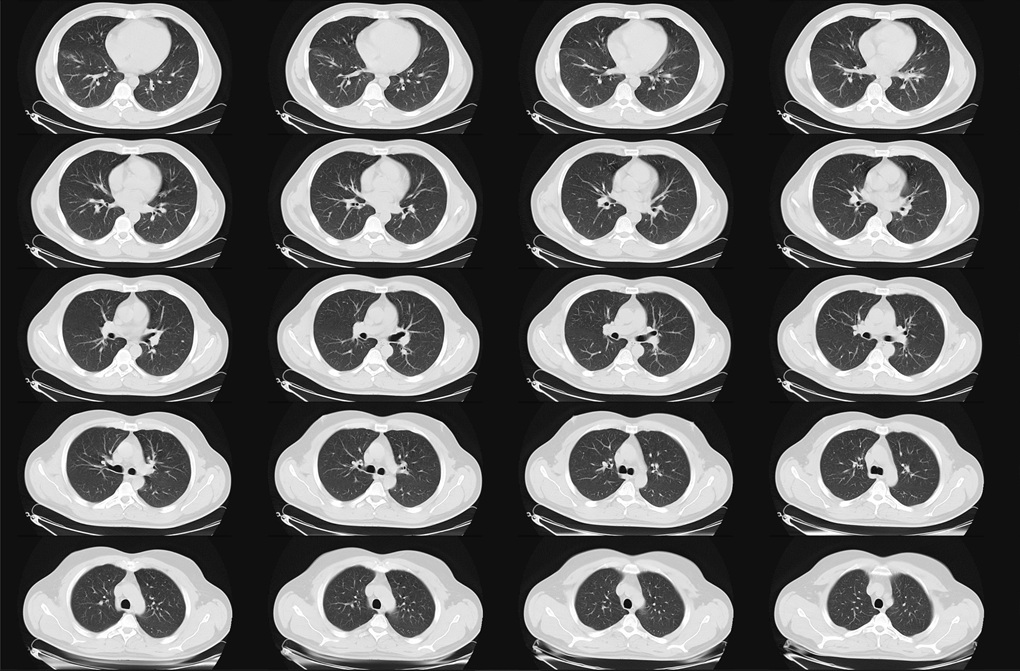

EULAR 2025 – pierwsze europejskie wytyczne dot. leczenia śródmiąższowej choroby płuc u pacjentów z chorobami tkanki łącznej